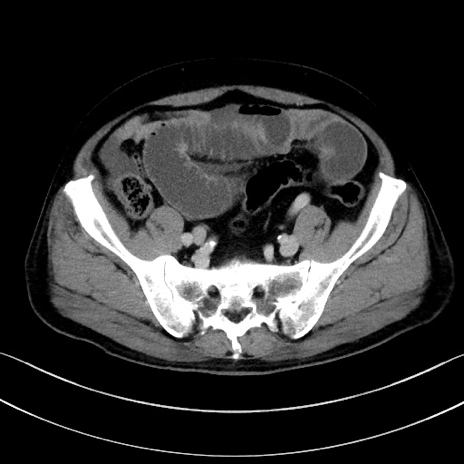

症例15(横断像)

【症例】70歳代男性

【主訴】腹痛

【現病歴】今朝から腹痛あり。全体的に痛い。特に左上の方。排ガスが今日はない。冷や汗が出る。

【既往歴】直腸癌術後

【身体所見】左側腹部〜上腹部に圧痛あり。腹膜刺激症状明らかなではない。軽度反跳痛。左下腹部に術後瘢痕あり。

【データ】WBC 7700、CRP 0.02